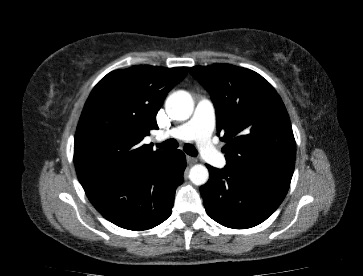

Мультиспиральная компьютерная томография – это современный высокоинформативный рентгенологический метод диагностики различной патологии легких. КТ основана на применении рентгеновского излучения. Однако в отличие от обычного рентгена, при котором снимки делаются в одной плоскости и изображения органов могут накладываться друг на друга, КТ лишена этих недостатков, так как во время компьютерной томографии сканирование проводится в различных плоскостях.

Во время исследования рентгеновская трубка томографа вращается вокруг исследуемой области и производит множество послойных снимков с шагом 0,5-1 мм. Полученные снимки поперечного сечения с помощью компьютерной программы могут быть преобразованы в 3D-изображения исследуемого органа или участка ткани. Это позволяет выявлять практически все заболевания легких на ранних стадиях и назначать своевременное лечение.

В некоторых случаях, например, при подозрении на опухолевый процесс, проводится КТ легких с контрастированием, когда для лучшей визуализации патологического очага пациенту внутривенно вводится йодсодержащий контрастный препарат. Контрастное вещество накапливается в патологических участках и обеспечивает их яркую визуализацию на фоне неизмененной ткани. С помощью контрастирования можно визуализировать кровеносные сосуды, выявить первичные опухоли и метастазы в легких, дифференцировать новообразования, например, отличить доброкачественную опухоль от злокачественной.

В медицинском центре «Доступная медицина» установлено современное оборудование – 64-срезовый и 128-срезовый компьютерные томографы TOSHIBA AQUILION, на которых проводится сканирование легочной ткани. За счет увеличенного количества детекторов аппараты производят снимки с большой скоростью и минимальной дозой облучения. При этом инновационные цифровые приложения позволяют получить объемные изображения легочной ткани высокой четкости, контрастности и в мельчайших подробностях.